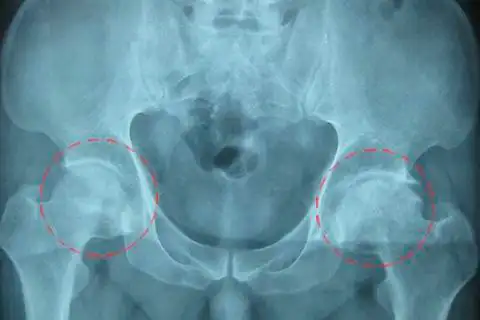

增高治疗前x光片:患者左侧股骨头塌陷,碎裂,变形,股骨颈骨皮质不连